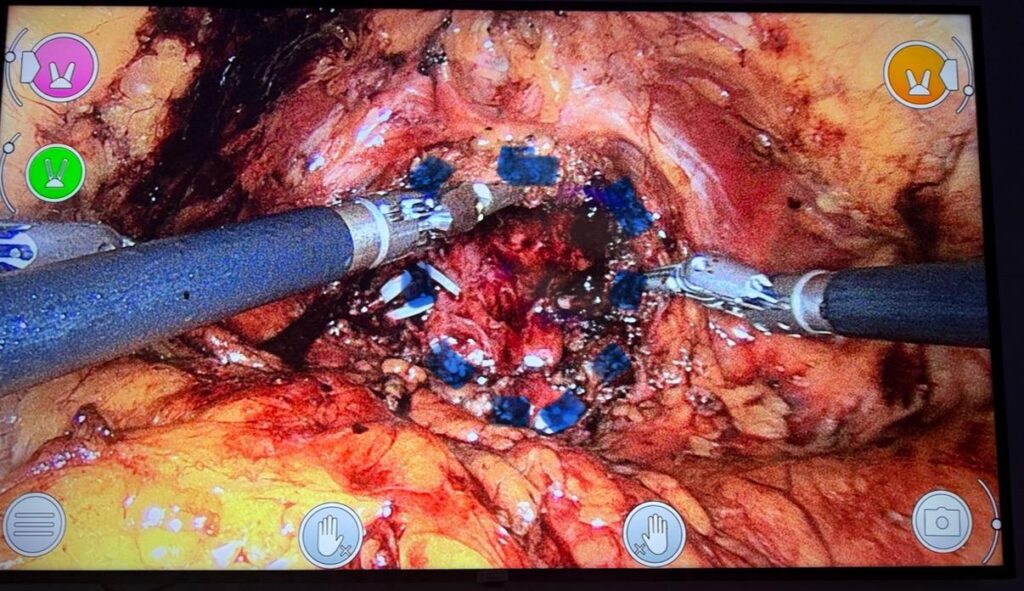

A tecnologia permitiu tratamentos mais precisos e menos invasivos. A cirurgia robótica da próstata, realizada pelo Dr. Yoann Pérès na Urocenter, oferece visão ampliada, movimentos mais delicados e melhor preservação de estruturas, contribuindo para menor sangramento, recuperação mais rápida, continência urinária e função sexual preservadas quando comparado a técnicas convencionais.

Figura 2 – Dr. Yoann Pérès em console robótico.

Figura 3 – Etapa intraoperatória de prostatectomia robótica (ultraconservação).